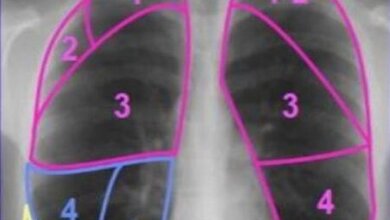

Segment Анатомия, семиотика. Рентген, КТ Часть легкого, вентилируемая сегментарным бронхом. Снабжается кровью через сегментарную легочную артерию, отток крови осуществляется в сегментарную вену между двумя соседними сегментами. В доле легкого может быть от 2 до 5 сегментов. Отдельные сегменты в норме не разделены висцеральной плеврой на рентгенограммах и КТ-срезах...